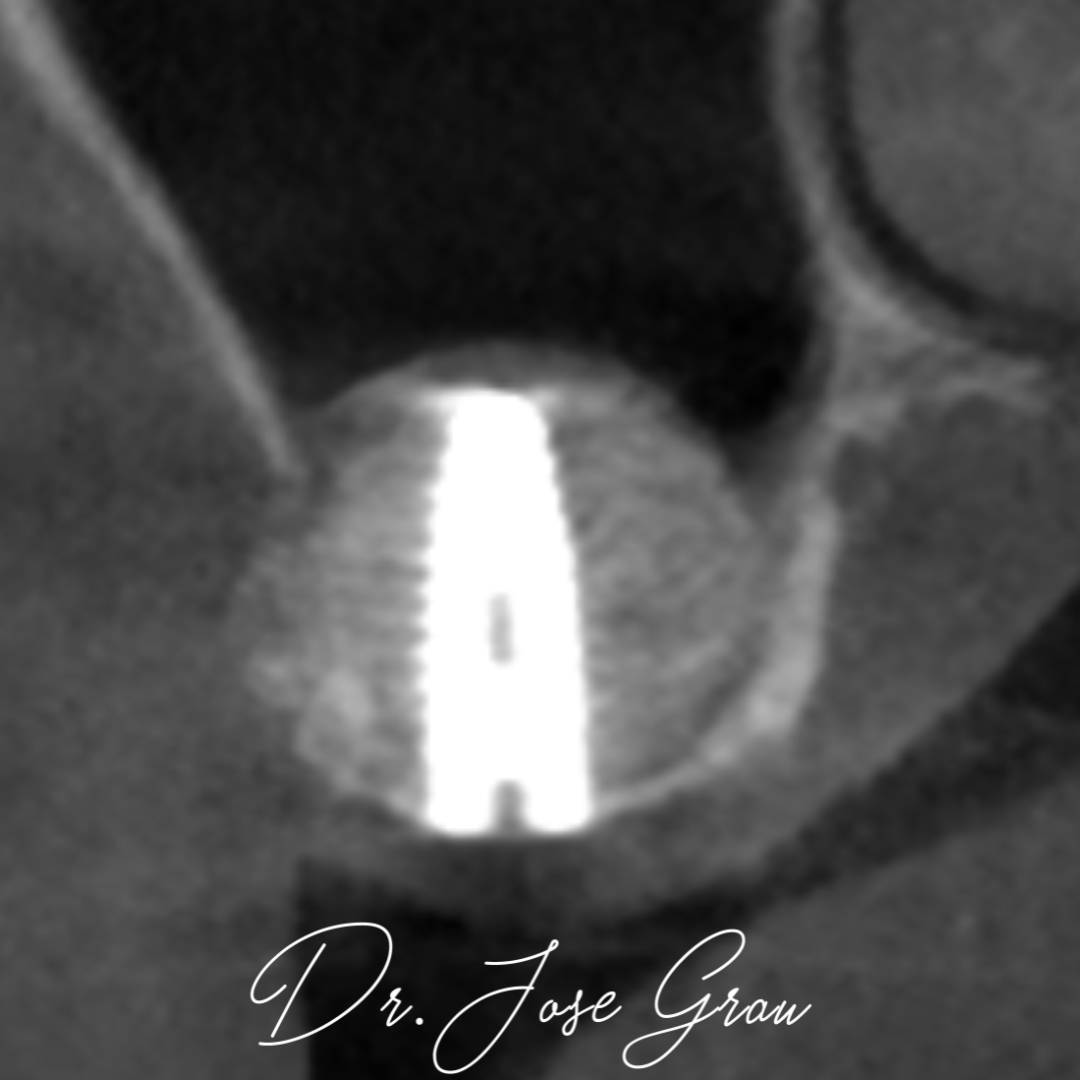

Elevación de seno